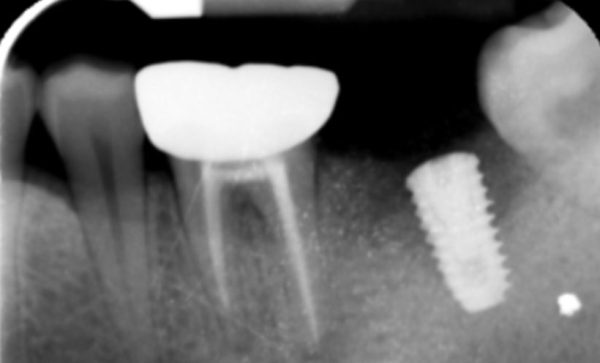

Case 20